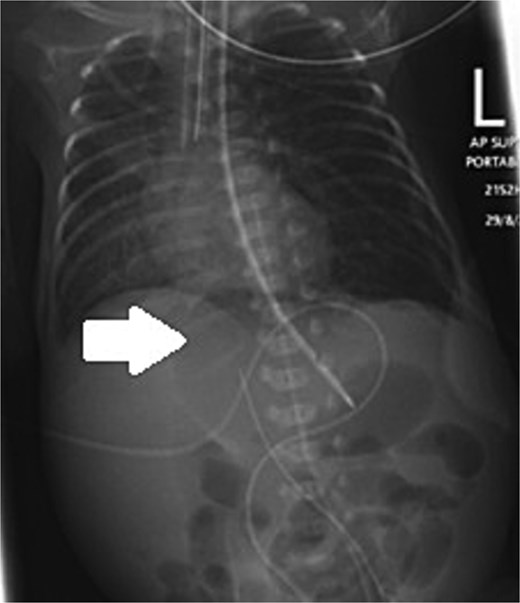

An extremely premature surviving twin baby, born at 23 weeks of gestation, was referred to our tertiary neonatal unit for advanced care. The baby weighed 560 g. He was intubated and ventilated immediately, followed by an uneventful umbilical arterial catheter and umbilical venous catheter insertion. Trophic feeds were started on Day 4 of life. Formula feeding started on Day 7. The baby passed meconium on Day 8 and abdominal distention was noted on the same day. On Day 10, the baby developed raised inflammatory markers, hyponatremia, and acidosis. The feeding was stopped, and antibiotics were started. On Day 11, he developed septic shock. Supine and lateral decubitus abdominal X-ray was done, which showed free air, confirming intestinal perforation (Fig. 1).

Supine and lateral decubitus abdominal X-rays on Day 11 of life showing free air (arrow), confirming intestinal perforation.